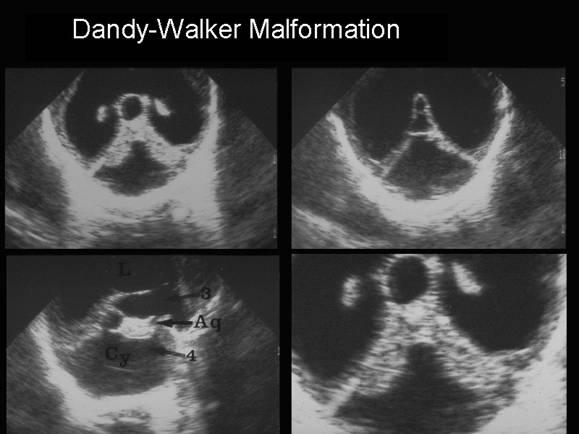

МРТ снимки мальформации Денди-Уокера